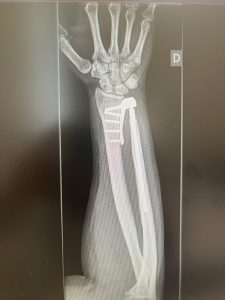

PATOLOGIAS MUÑECA - PRÓTESIS ARTICULARES Figura 1 - Prótesis radio-carpiana de 4ª generación

Figura 1 - Prótesis radio-carpiana de 4ª generación